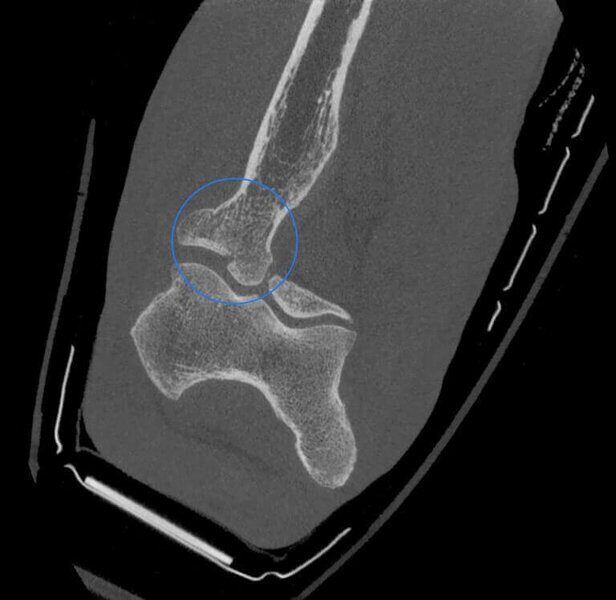

Fractura de la cabeza del radio en paciente con yeso.